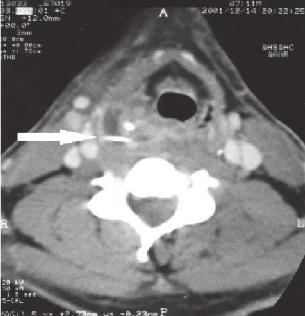

▲箭头指的是鱼刺以及鱼刺引起的周围脓肿